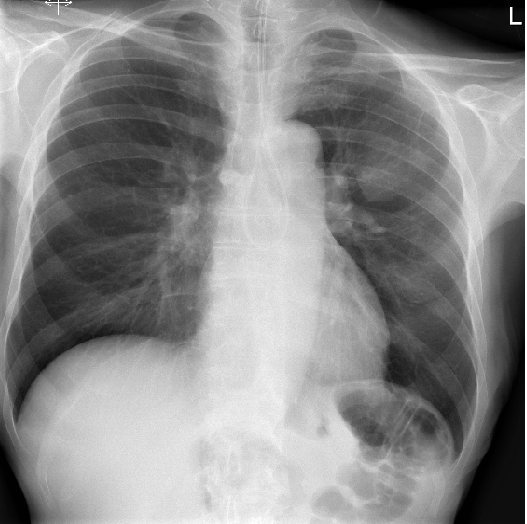

Chest Xray, posteroanterior view, showing marked cardiomegaly Identifying Carina On X Ray Trachea, carina, bronchi and hilar structures. How to find the carina on a frontal chest radiograph • follow the right or left main bronchus backward until it meets the opposite main bronchus. The carina is a cartilaginous ridge at the tracheal bifurcation, serving as an important reference point in chest imaging. Correct positioning of a cvc tip. The carina projects. Identifying Carina On X Ray.